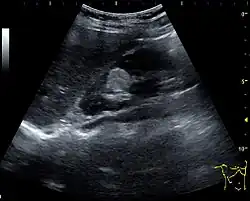

Complex cysts can have membranes dividing the fluid-filled center with internal echoes, calcifications or irregular thickened walls. The complex cyst can be further evaluated with Doppler US, and for Bosniak classification and follow-up of complex cysts, either contrast-enhanced ultrasound (CEUS) or contrast CT is used (Figure 6). The Bosniak classification is divided into four groups going from I, corresponding to a simple cyst, to IV, corresponding to a cyst with solid parts and an 85–100% risk of malignancy.[1] In polycystic kidney disease, multiple cysts of varying size in close contact with each other are seen filling virtually the entire renal region. In advanced stages of this disease, the kidneys are enlarged with a lack of corticomedullary differentiation (Figure 7).[1]